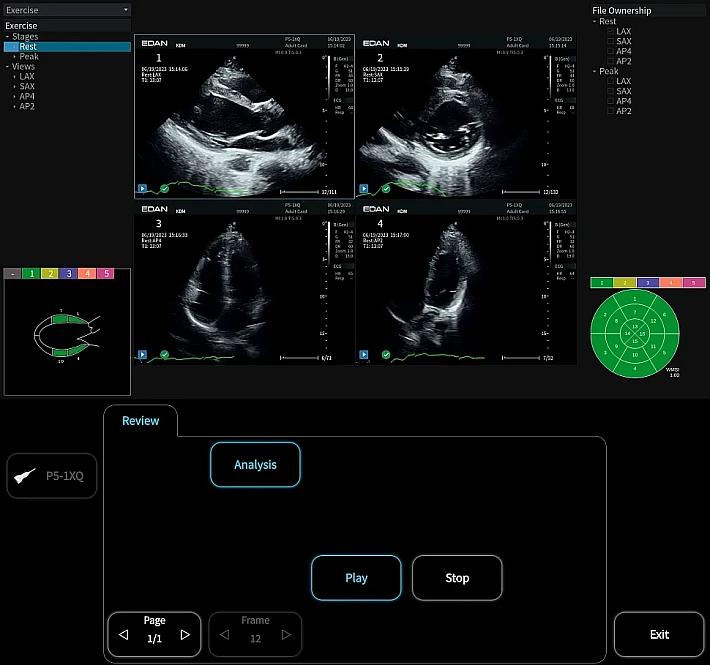

Медицинское оборудование и сервисное обслуживание